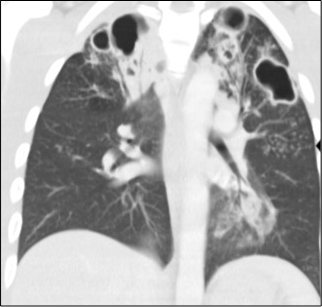

Porque afecta a los pulmones y otros órganos. Además, se presenta en personas que pueden tener un déficit de la inmunidad como desnutrición, infección por el VIH o diabetes, y a otros con trastornos por consumo de alcohol y tabaquismo. Por otro lado, el diagnóstico puede ser tardío o hay pacientes que abandonan el tratamiento.

A nivel global, el número de casos de tuberculosis notificados se redujo en un 18% el año 2020 con respecto al año anterior (disminuyó significativamente el numero de exámenes realizados) y la cantidad de muertes por esta causa mostró un aumento en el mismo año.

La tuberculosis nunca ha desaparecido en Chile y mantiene tasas de enfermedad de más de 10 casos por 100.000 habitantes. En los últimos años, el Programa Nacional Contra la Tuberculosis favoreció el uso de la PCR como prueba de diagnóstico inicial, en vez de la baciloscopía. La PCR tiene mayor sensibilidad y el diagnóstico es más rápido, con lo cual mejoró su detección. Así, los casos de tuberculosis pulmonar con confirmación por PCR subieron de 54% el año 2020 a 83% el año 2021.